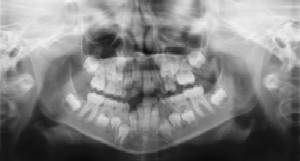

Radiographs (X-Rays) are a vital and necessary part of your child’s dental diagnostic process. Without them, certain dental conditions can and will be missed.

Dental Radiographs (X-Rays)

Radiographs detect much more than cavities. For example, radiographs may be needed to survey erupting teeth, diagnose bone diseases, evaluate the results of an injury, or plan orthodontic treatment. Radiographs allow dentists to diagnose and treat health conditions that cannot be detected during a clinical examination. If dental problems are found and treated early, dental care is more comfortable for your child and more affordable for you.

The American Academy of Pediatric Dentistry recommends radiographs and examinations every six months for children with a high risk of tooth decay. On average, most pediatric dentists request radiographs approximately once a year. Approximately every 3 years, it is a good idea to obtain a complete set of radiographs, either a panoramic and bitewings or periapicals and bitewings.

Pediatric dentists are particularly careful to minimize the exposure of their patients to radiation. With contemporary safeguards, the amount of radiation received in a dental X-ray examination is extremely small. The risk is negligible. In fact, the dental radiographs represent a far smaller risk than an undetected and untreated dental problem. Lead body aprons and shields will protect your child. Today’s equipment filters out unnecessary x-rays and restricts the x-ray beam to the area of interest. High-speed film and proper shielding assure that your child receives a minimal amount of radiation exposure.